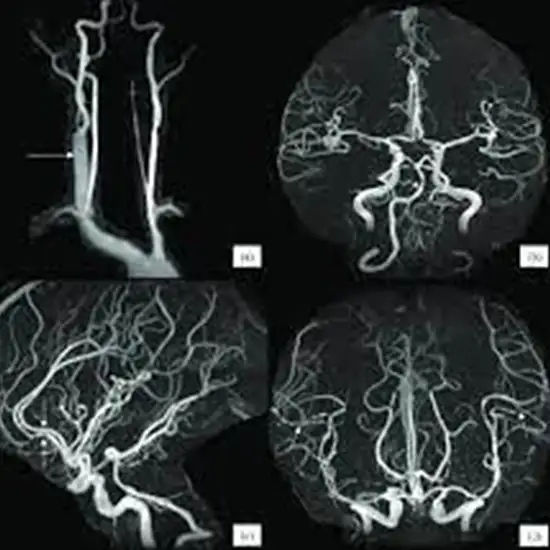

MR Angiography intra and extra-cranial is an imaging procedure of the brain. This scan is performed to evaluate the blood vessels that carry blood up from the heart to the base of the skull and the blood vessels that lead to the brain. It helps in diagnosing the conditions such as blood clotting, aneurysm, stenosis, etc.